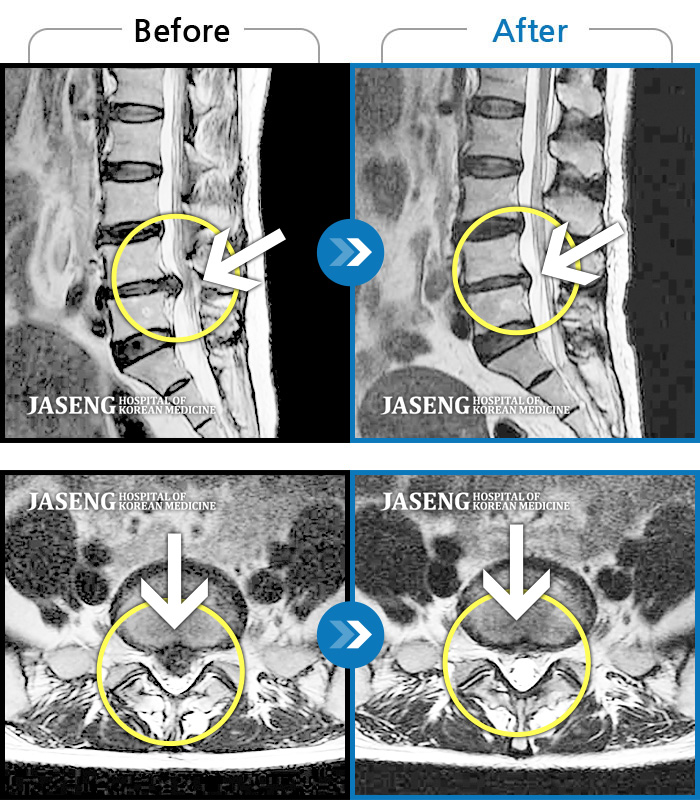

7월 중순경 허리디스크때문에 걷지도 앉지도 못하고 잠도 못 잘만큼 고통 이 심했는데 침과 추나요법 치료를 받고 지금은 통증없이 잘 지내고 있습니다...

친절하게 잘 치료해주신 김 민수 원장님께 감사드립니다~~